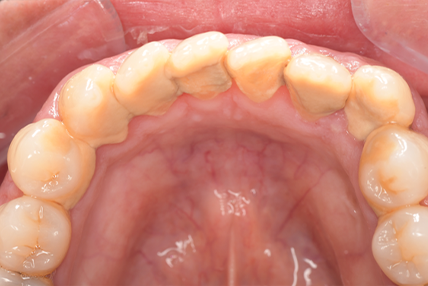

CASE 2

Before

After

基本情報

| 年齢・性別 | 30代・男性 |

| 主訴 | 歯石を取りたい |

| 治療内容 | 超音波スケーラーでの歯石除去 |

| 治療期間 | 60分 |

| 治療費 | 初診料を含め約4,500円 |

| リスク・副作用 | 歯ぐきに違和感や痛みを覚える場合がある。 1週間程度、歯を磨くといつもより出血することがある。 腫れていた歯ぐきが引き締まることで歯ぐきが下がった様に見える。 歯ぐきが下がることで歯がみしやすくなることがある。 一時的に歯の動揺(ゆれ)が増す場合がある。 |